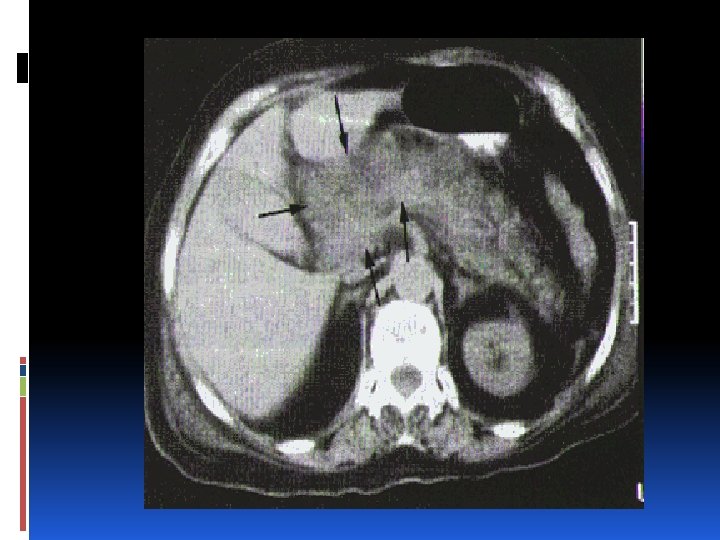

Radiología Gold standar: Tomografía Axial Computarizada contraste IV. Brinda información sobre: Configuración de la glándula y la existencia o progresión de exudados. TAC Dinámica: Disminución en captación de contraste IV= Pancreatitis Necrohemorrágica.

Radiología ¿Cuándo debemos indicar una TAC? Signos de Pancreatitis Aguda Severa. Ausencia de mejoría clínica a las 72 horas. Duda diagnóstica. Sospecha de infección: Fiebre mayor de 38° Tipo de TAC: contraste IV ¿Qué buscamos con la misma? Necrosis: Disminución en captación de contraste. Colección líquida Diagnósticos alternativos. Pronóstico. Establecer severidad.

CLASIFICACIÓN DE TOMOGRÁFICA DE BALTHAZAR.

Complicaciones locales: Necrosis Pancreática: Diagnosticada por TAC contraste I. V. 1. Estéril 2. Infectada Pseudoquiste Pancreático: Colección líquida de secreción pancreática con pared no epitelial. Sospechar en pancreatitis que no mejora en una semana. Pocos requieren tratamiento quirúrgico. Aspirar los de rápido crecimiento. 50% se resuelven en forma espontánea.